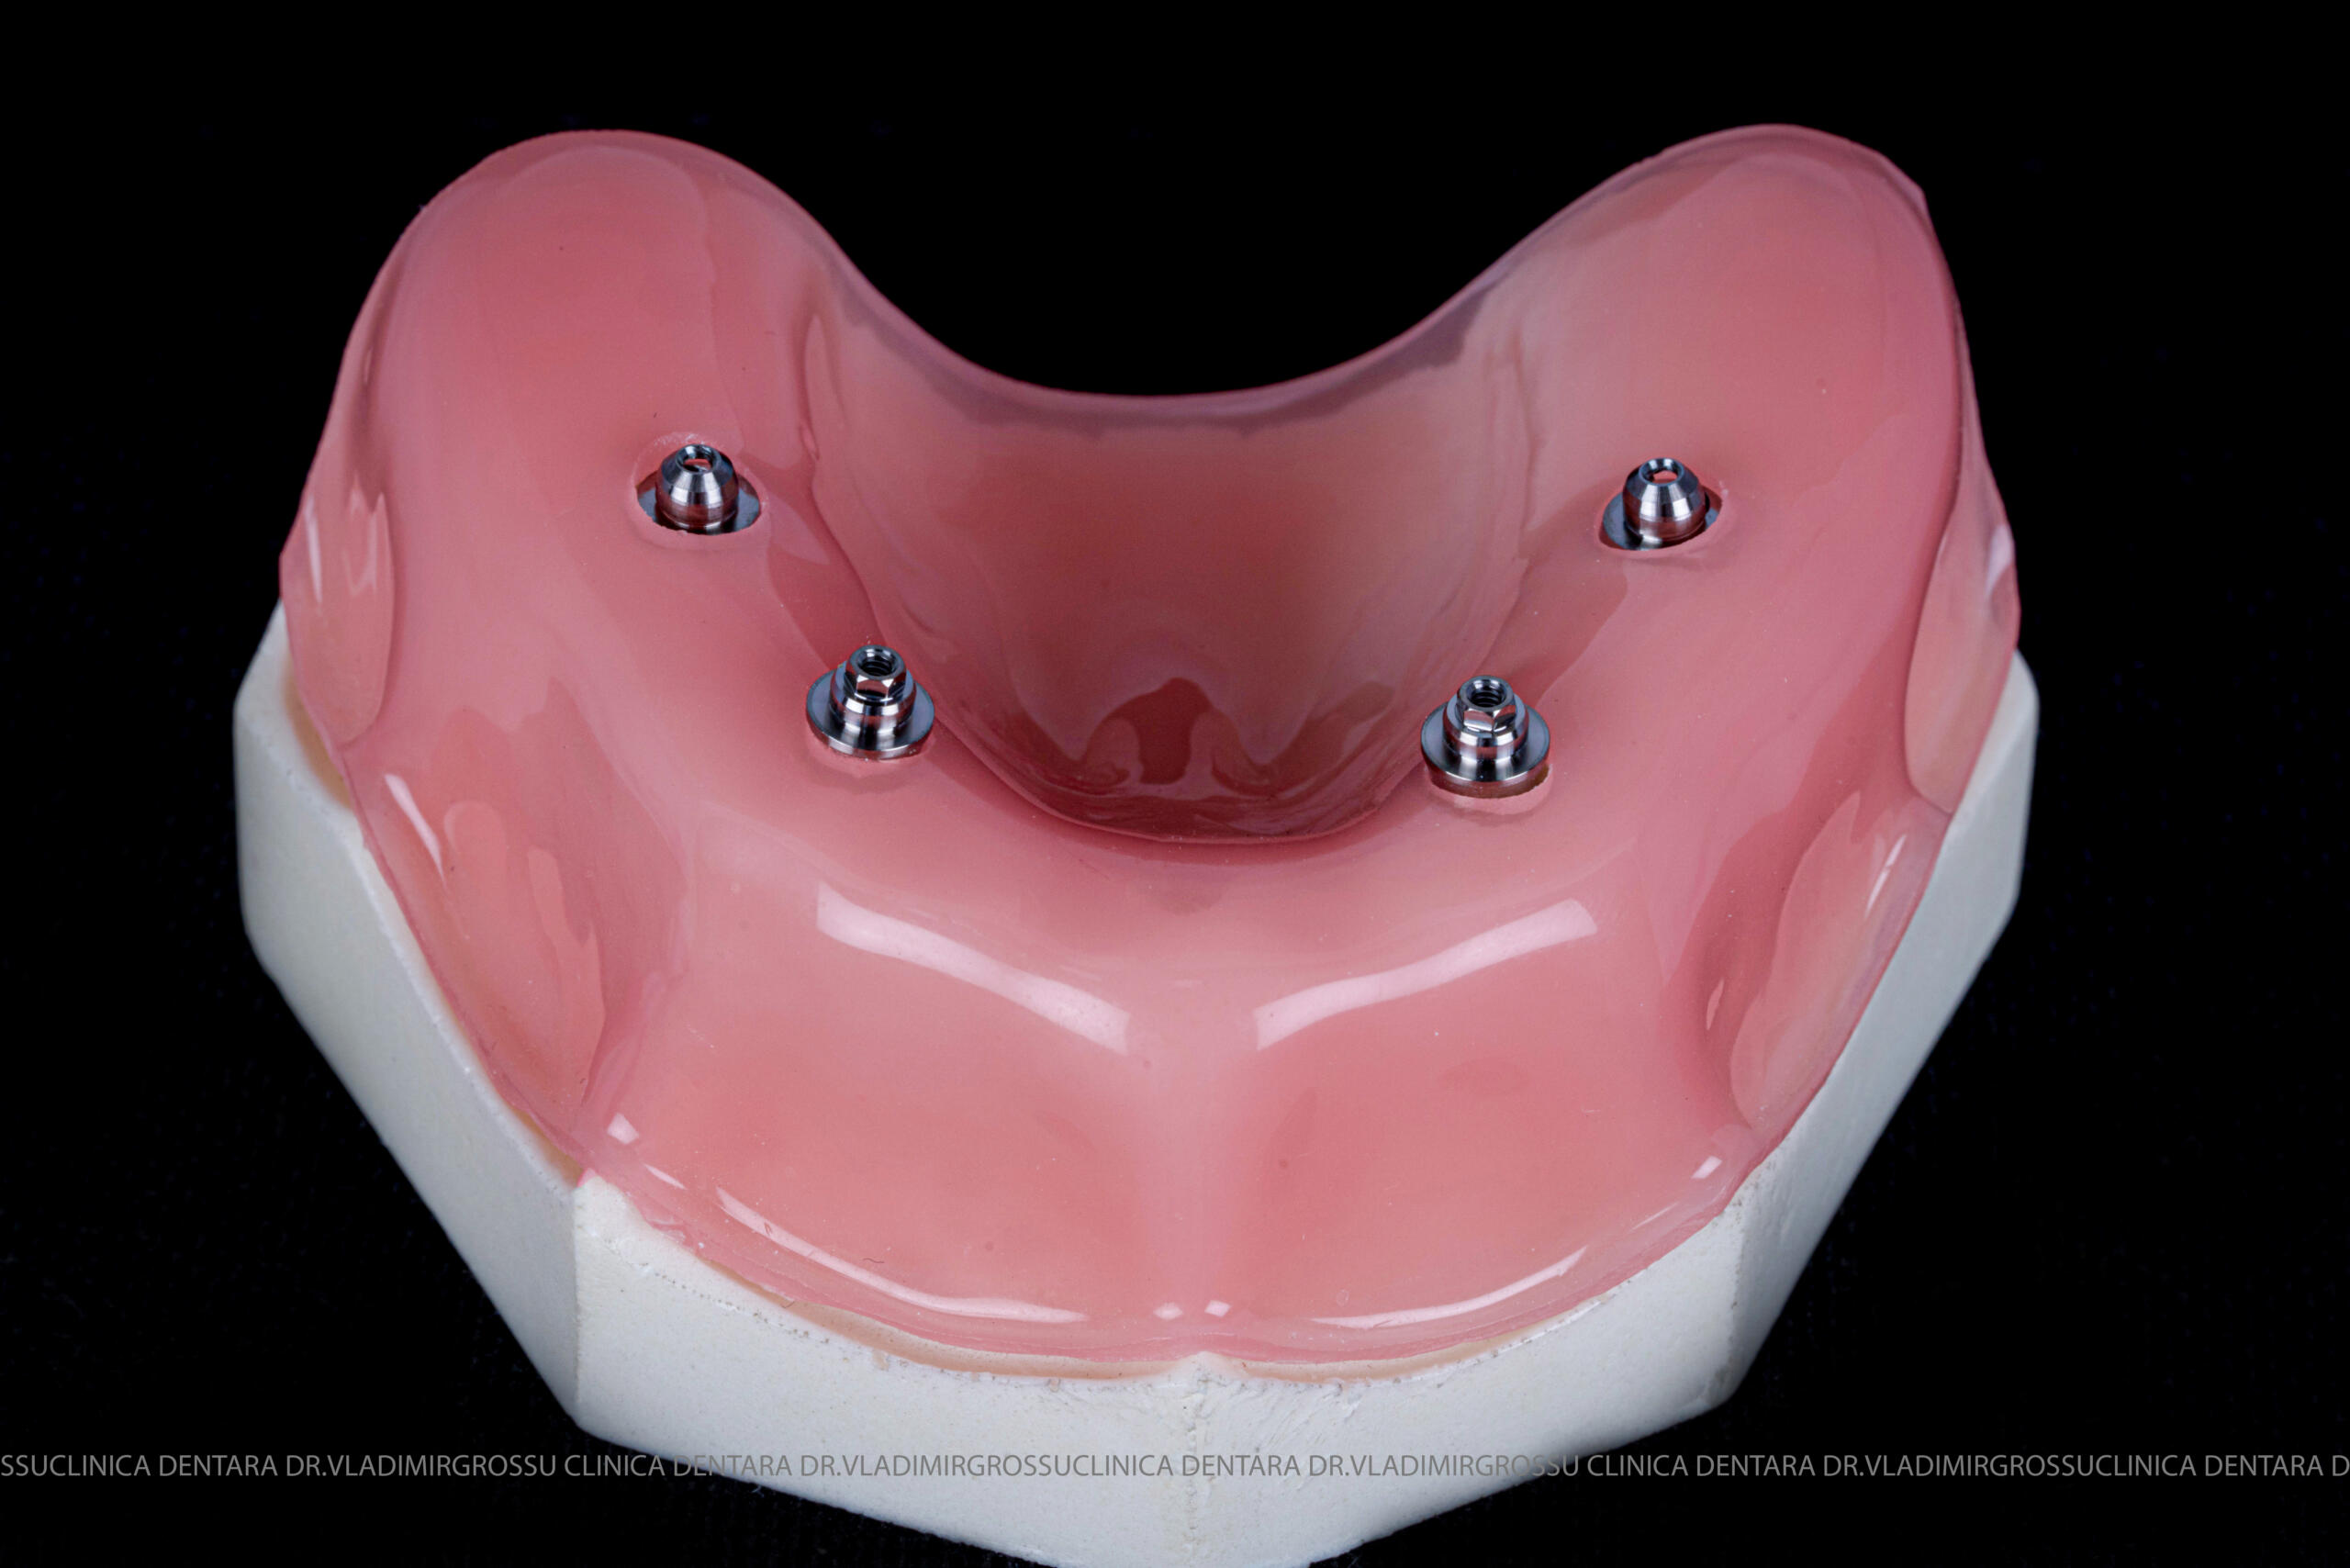

studii științifice.În cazurile de atrofie osoasă severă, când inserarea implanturilor în zonele laterale nu este posibilă fără adăugare osoasă, conceptul All-on-4 prevede plasarea implanturilor în unghiuri strategice pentru a evita zonele deficitare. Astfel, două implanturi sunt plasate în zona incisivilor laterali, iar alte două în zona premolarilor.

- 4 implanturi;

- 2 multiunit-uri drepte și 2 multiunit-uri angulate, conform necesităților protetice;

- 4 abutment-uri provizorii pe multiunit-uri;

- Proteză provizorie din masă plastică frezată sau proteză mobilizabilă pregătită și ajustată la componentele protetice.

Pentru proteza definitivă:

- 4 abutment-uri permanente pe multiunit-uri;

- Proteză definitivă din metaloceramică sau zirconiu pe o structură metalică, cu 12 unități (soluția recomandată).